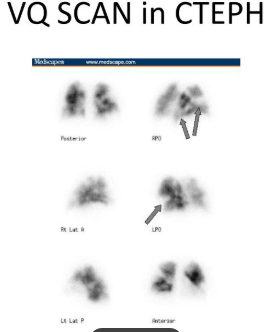

This Group of Pulmonary Hypertension is associated with CTEPH.

Group 4